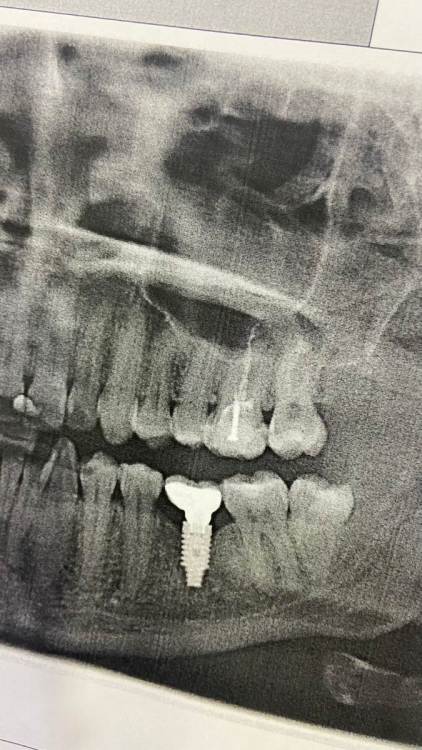

В октябре 2021 года был установлен имплантат, в январе 2022 поставили формирователь, в феврале  2022 установлена коронка.

Вчера пришла в другую клинику на плановую гигиену, сделали снимок для общей картины и тут выяснилось, что костная ткань под коронкой имеет чашеобразный дефект.

Мнения, как это и бывает, сразу же разошлись. Одни говорят надо переделывать, другие все оставить как и есть, раз нет никаких жалоб, просто наблюдать и следить за гигиеной.